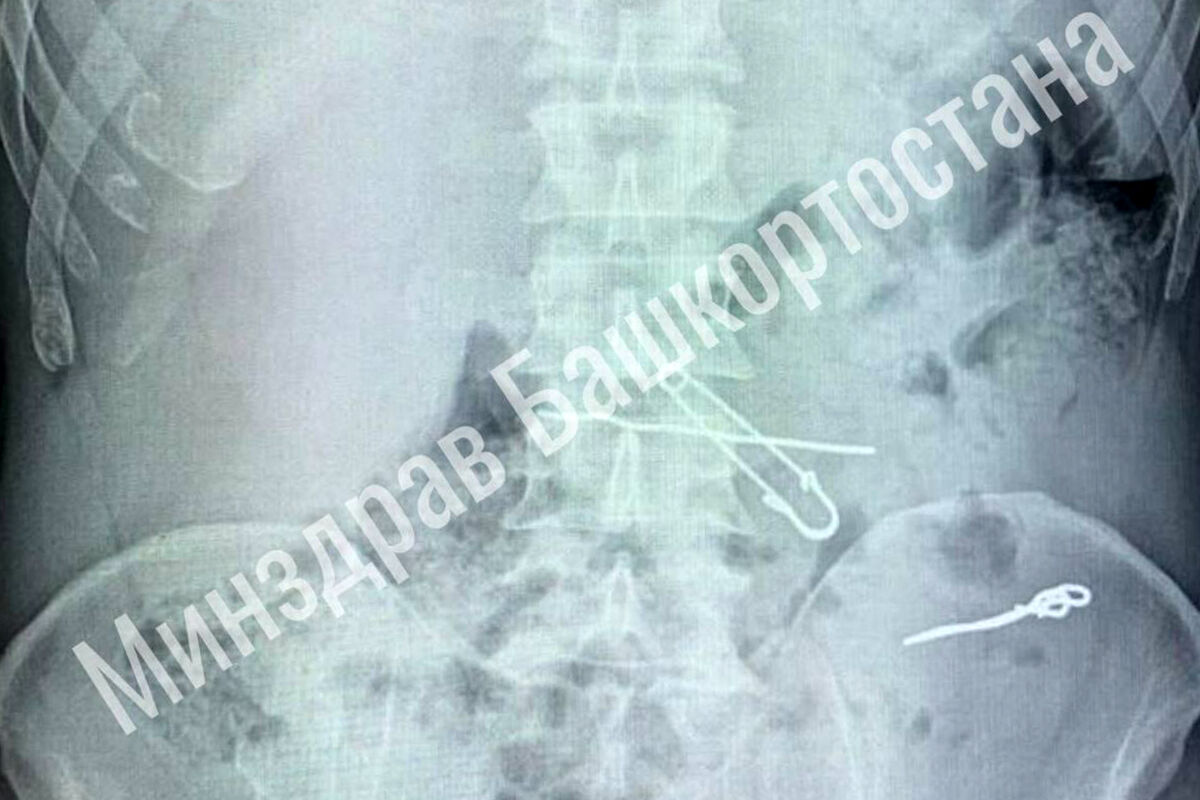

В больницу скорой медицинской помощи поступил мужчина с жалобами на сильные боли в животе. По результатам обследования выяснилось, что у него в толстой кишке находились три металлические скрепки длиной 47, 62 и 90 миллиметров, а в желудке — булавка и проволока.

Пациента срочно госпитализировали в отделение гнойной хирургии, где врачи успешно провели операцию по извлечению всех предметов. Во время вмешательства медики делали контрольные рентгеновские снимки, чтобы убедиться в полном удалении инородных тел. После операции мужчина успешно восстановился и был выписан из медицинского учреждения.